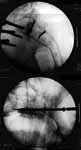

I am attaching the postop CT axial and coronal cuts with 2 iliosacral

screws in situ. I think there is probably 1 cm or so of upward movement at

the fracture site looking at it, but the II pics on table were not showing

it, so I decided to fix it in the same position without changing the exfix

alignment and just compressed the fracture site ever so slightly only. the

postop CT cuts were accomplished by our helpful radiologist who wanted the

images just as much as me, so we did it on "academic", no charge basis!